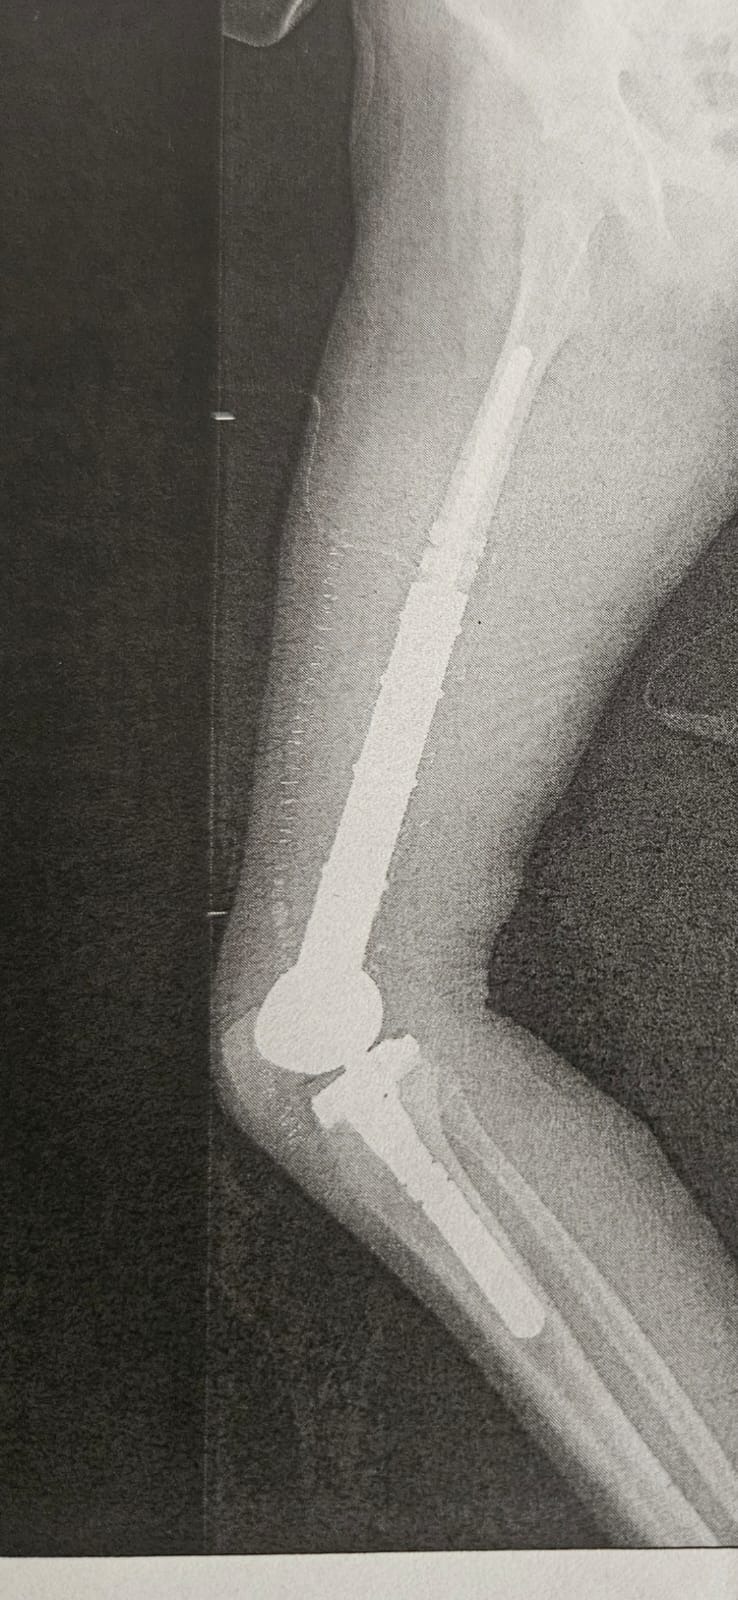

Lea hat bereits neun Chemotherapien durchgestanden, jede einzelne ein schwerer Schritt auf ihrem Weg. Im August 2025 wurde sie operiert, wobei 22 cm ihres Oberschenkelknochens entfernt und durch eine Prothese ersetzt wurden. Die Operation verlief erfolgreich, doch Lea’s Reise ist noch nicht zu Ende: Im September 2025 beginnt ihre zehnte Chemotherapie, und insgesamt sind noch fünf weitere Chemotherapien geplant. Neben der schulmedizinischen Behandlung setzen wir auf Heilpraktiker und Mikronährstoffe, die gute Ergebnisse zeigen, aber leider nicht von der Krankenkasse übernommen werden. Die hohen Kosten für diese Behandlungen, die vielen Fahrten zum Krankenhaus und die Gehaltseinbußen durch Krankengeld belasten uns finanziell stark.